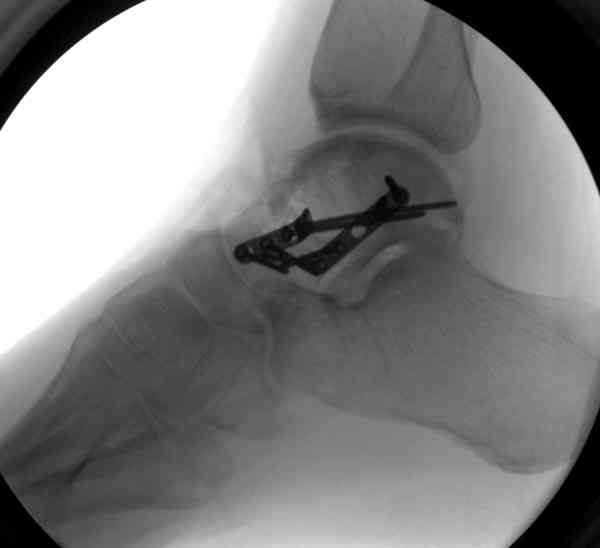

Случай с множественным оскольчатым переломом тарана оперированный из двойного доступа.

Через 2 мес.: